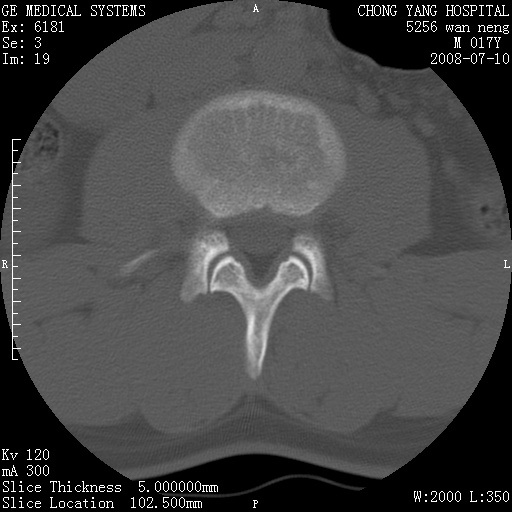

腰3、4椎弓崩裂

腰3、4椎弓不连

支持:腰3、4椎弓峡部崩裂。

腰3、4椎弓峡部不连

支持:腰3、4椎弓峡部崩解。

腰3、4,如受过外伤则为陈旧骨折,否则为骨质不连

图片漂亮,目前也只能看到腰3、4骨质不连

腰3、4椎弓峡部裂。

腰3、4椎弓峡部裂。支持

重建图像见多个椎弓峡部不连(不足为据),平扫未见异常。

支持腰3、4椎弓峡部崩裂。